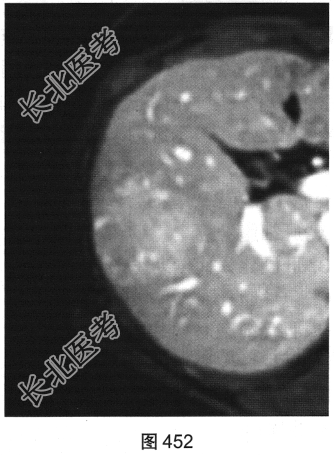

- 多项选择题3.[提示]随后患者接受上腹部MRI检查,如图449~图452所示。对患者MRI检查图像描述不正确的是( )

A、纤维瘢痕呈延迟强化

B、门静脉期病灶轻度强化

C、T1WI示病灶为稍低信号

D、动脉期病灶明显强化

E、T2WI示病灶为稍高信号

F、病灶内无纤维瘢痕